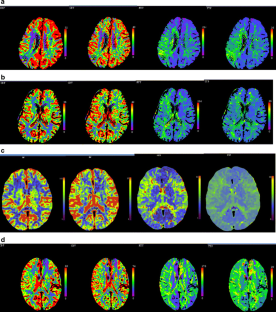

CTP was performed on 19 patients, comprising 10 patients with moyamoya disease and nine patients with occlusive cerebrovascular disease, preoperatively and on the third postoperative day. According to the regional cerebral microcirculatory change and modality of CTP, the regional cerebral ischemic status was graded into two stages with four substages (I1, I2, II1, and II2) to indicate the regional cerebral perfusion and ischemic status of the patients. The ischemic status was analyzed in all 19 patients according to those stages preoperatively and postoperatively.

Among the 19 patients, nine (47.4%) showed improvement in the regional cerebral ischemic status, six (31.6%) showed no change, and four (21.1%) showed deterioration. Both improvement and no change in the regional cerebral ischemic status were regarded as effective, while deterioration was regarded as ineffective, meaning that 15 (78.9%) patients were effective and four (21.1%) patients were ineffective. The effective rate for moyamoya disease (one of ten, 90.0%) was significantly higher than that for occlusive cerebrovascular disease (three of nine, 66.7%). Postoperatively, only one patient (case N11) exhibited deterioration of symptoms, which presented as right hemiplegia and aphasia, and no obvious changes in symptoms were observed for the other patients in the transient period.

This study has shown that STA-MCA bypass is an effective and safe way to improve the regional cerebral perfusion and ischemic status in ischemic cerebrovascular diseases. The stage based on the regional cerebral microcirculatory change and presentation of CTP can directly reflect the pathological mechanism underlying the regional cerebral ischemic status.